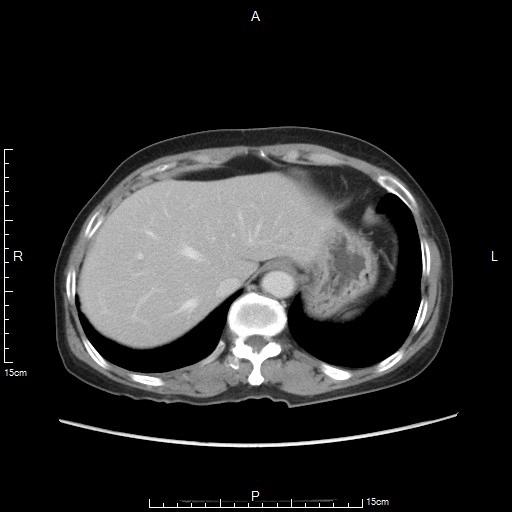

- 复查CT显示胃部肿瘤明显坏死

CT显示胃部肿瘤大片坏死灶

CT显示胃部肿瘤明显缩小